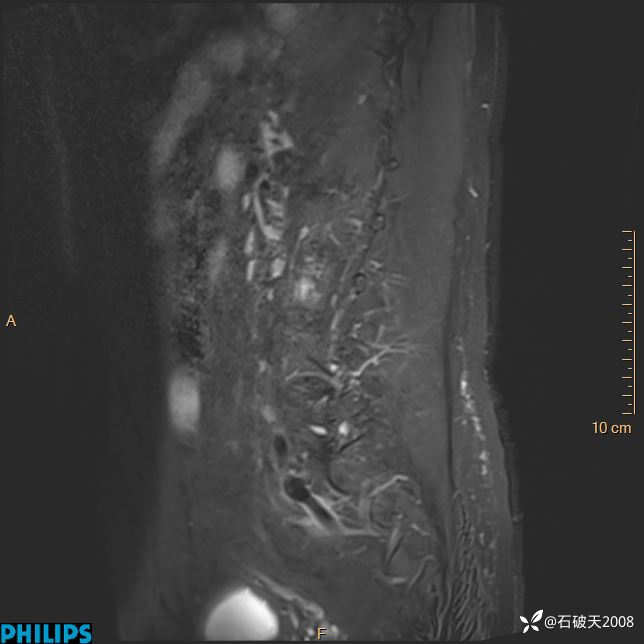

2023年3月份MRI影像

T2矢状位压脂